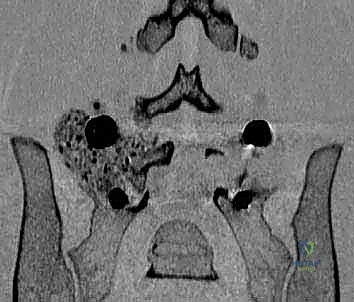

لفهم كيفية عمل تقنيات PLIF و TLIF، يجب أولاً فهم تشريح العمود الفقري القطني. يتكون الجزء السفلي من الظهر من خمس فقرات قطنية (L1 إلى L5). بين كل فقرة وأخرى يوجد "قرص غضروفي" (Disc) يعمل كوسادة لامتصاص الصدمات وتسهيل الحركة. يمر الحبل الشوكي والأعصاب الشوكية عبر قناة عظمية تُسمى "القناة الشوكية".

عندما تتآكل هذه الأقراص الغضروفية بسبب التقدم في العمر أو الإصابات، أو عندما تتحرك الفقرات من مكانها الطبيعي، يحدث تضيق في القناة الشوكية أو ضغط مباشر على جذور الأعصاب. هذا الضغط الميكانيكي هو المسبب الرئيسي للألم المبرح الذي يمتد غالبًا إلى الساقين (ما يُعرف بعرق النسا).

في هذه التقنية، يتم الوصول إلى العمود الفقري من الخلف مباشرة. يقوم الجراح بإزالة جزء من العظم (الصفيحة الفقرية Laminectomy) للوصول إلى القناة الشوكية. يتم سحب الأعصاب برفق إلى الجانبين للوصول إلى القرص التالف وإزالته، ثم يتم إدخال "أقفاص" (Cages) مدعومة بطعوم عظمية من كلا الجانبين.

الخطوة 2: إزالة الضغط العصبي (Decompression)

يقوم د. هطيف بإزالة الأجزاء العظمية الضاغطة (Laminectomy أو Facetectomy) والأربطة المتضخمة بدقة ميكروسكوبية لتحرير الأعصاب الشوكية المختنقة.